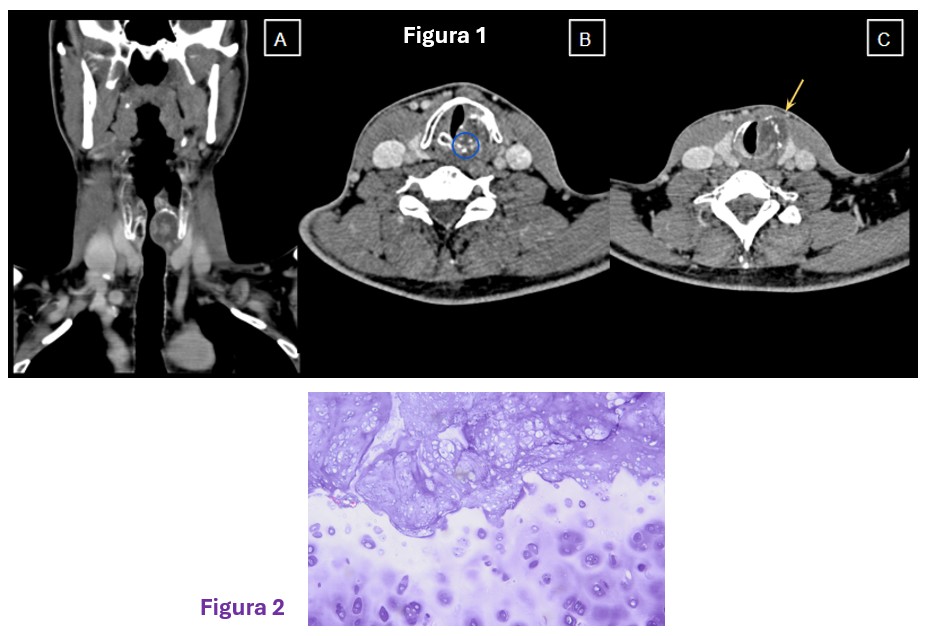

Resonancia magnética: secuencias ponderadas en T1 con gadolinio en plano axial (A), sagital (B) y coronal (C): Masa extraaxial de aspecto heterogéneo, bien definida, con un intenso realce periférico, de 42 x 41 x 38 mm (AP x TR x CC) en la línea media frontobasal. La lesión está en contacto con la lámina cribiforme y parece originarse del bulbo y tracto olfatorio izquierdo. Aisladas formaciones quísticas periféricas. Secuencia ponderada en T2 plano coronal (D): extensa área de hiperseñal T2 que se extiende por la sustancia blanca del lóbulo frontal izquierdo.

La RM es la técnica de elección para su diagnóstico, mostrando una masa extraaxial bien delimitada, de intensidad baja o intermedia en imágenes ponderadas en T1 e hiperintensas en T2. La hiperintensidad en T2 puede ser homogénea o mostrar un aspecto “en diana” con alta intensidad en la periferia de la lesión.

El diagnóstico diferencial debe incluirse con otros tumores extraaxiales con realce de localización subfrontal en la fosa anterior, que incluyen meningioma, adenoma quístico y, en raras ocasiones, estesioneuroblastoma. El schwannoma del bulbo o tracto olfativo es excepcional. Adicionalmente, se debe realizar el diagnóstico diferencial con los tumores intraaxiales (incluyendo el glioblastoma IDH wildtype).